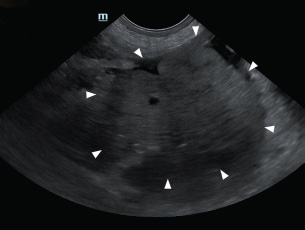

To correct hypovolemic shock prior to surgery, lactated Ringer’s solution was administered intravenously (IV) at a rate of 90 ml/kg/hour. Additionally, one unit of whole blood was transfused to restore circulating volume. Premedication consisted of butorphanol (0.2 mg/kg IV; Butophan Inj., Myungmoon Pharm. Co., Ltd., Seoul, Republic of Korea) and cefazolin (30 mg/kg IV; Safdin, Daehan New Pharm Co., Ltd, Republic of Korea). Anesthesia was induced with propofol (6 mg/kg IV; Provive 1%, Myungmoon Pharm. Co., Ltd., Seoul, Republic of Korea) and maintained with 1.2%–1.4% isoflurane (Forane sol., Choongwae. Co., Ltd., Seoul, Republic of Korea) delivered in 100% oxygen. Lactated Ringer’s solution was administered at 10 ml/kg/hour IV throughout the surgical procedure. Exploratory laparotomy via a ventral midline incision confirmed the presence of hemoperitoneum (Fig. 3). A firm, round, lobulated mass measuring 6 cm in height, 7 cm in width, and 8.5 cm in length was identified in the right pancreatic lobe. The mass was firmly adhered to the jejunal mesentery and adjacent mesenteric vessels (Fig. 4), consistent with its location in the caudal portion of the right pancreatic limb. Active bleeding was observed from a pancreatic vessel adjacent to the mass (Fig. 5). Blunt dissection with moistened cotton swabs was used to separate the right lobe from surrounding vessels. The pancreatic vessels were ligated using a bipolar vessel-sealing device (LigaSure; Valleylab, Tyco Healthcare Group, Boulder, CO, USA). A ligature was placed approximately 2 cm proximal to the tumor within the pancreatic parenchyma, and a portion of normal pancreas was excised. Approximately 13 cm of jejunum and the associated mesentery were also resected, followed by an end-to-end jejunal anastomosis. No gross metastatic lesions were observed in the liver or spleen. All excised tissues were fixed in 10% buffered formalin for histopathological examination.

Fig. 3. Exploratory laparotomy, using a ventral midline incision, confirmed hemoperitoneum (black arrowhead).